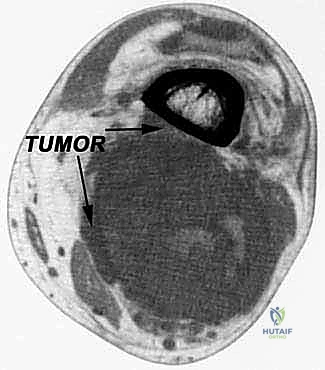

- التصوير بالرنين المغناطيسي (MRI) مع الصبغة: المعيار الذهبي لتشخيص أورام الأنسجة الرخوة. يحدد الـ MRI بدقة متناهية حجم الورم، حدوده، ومدى قربه أو غزوه للعظام، الأعصاب، والأوعية الدموية.